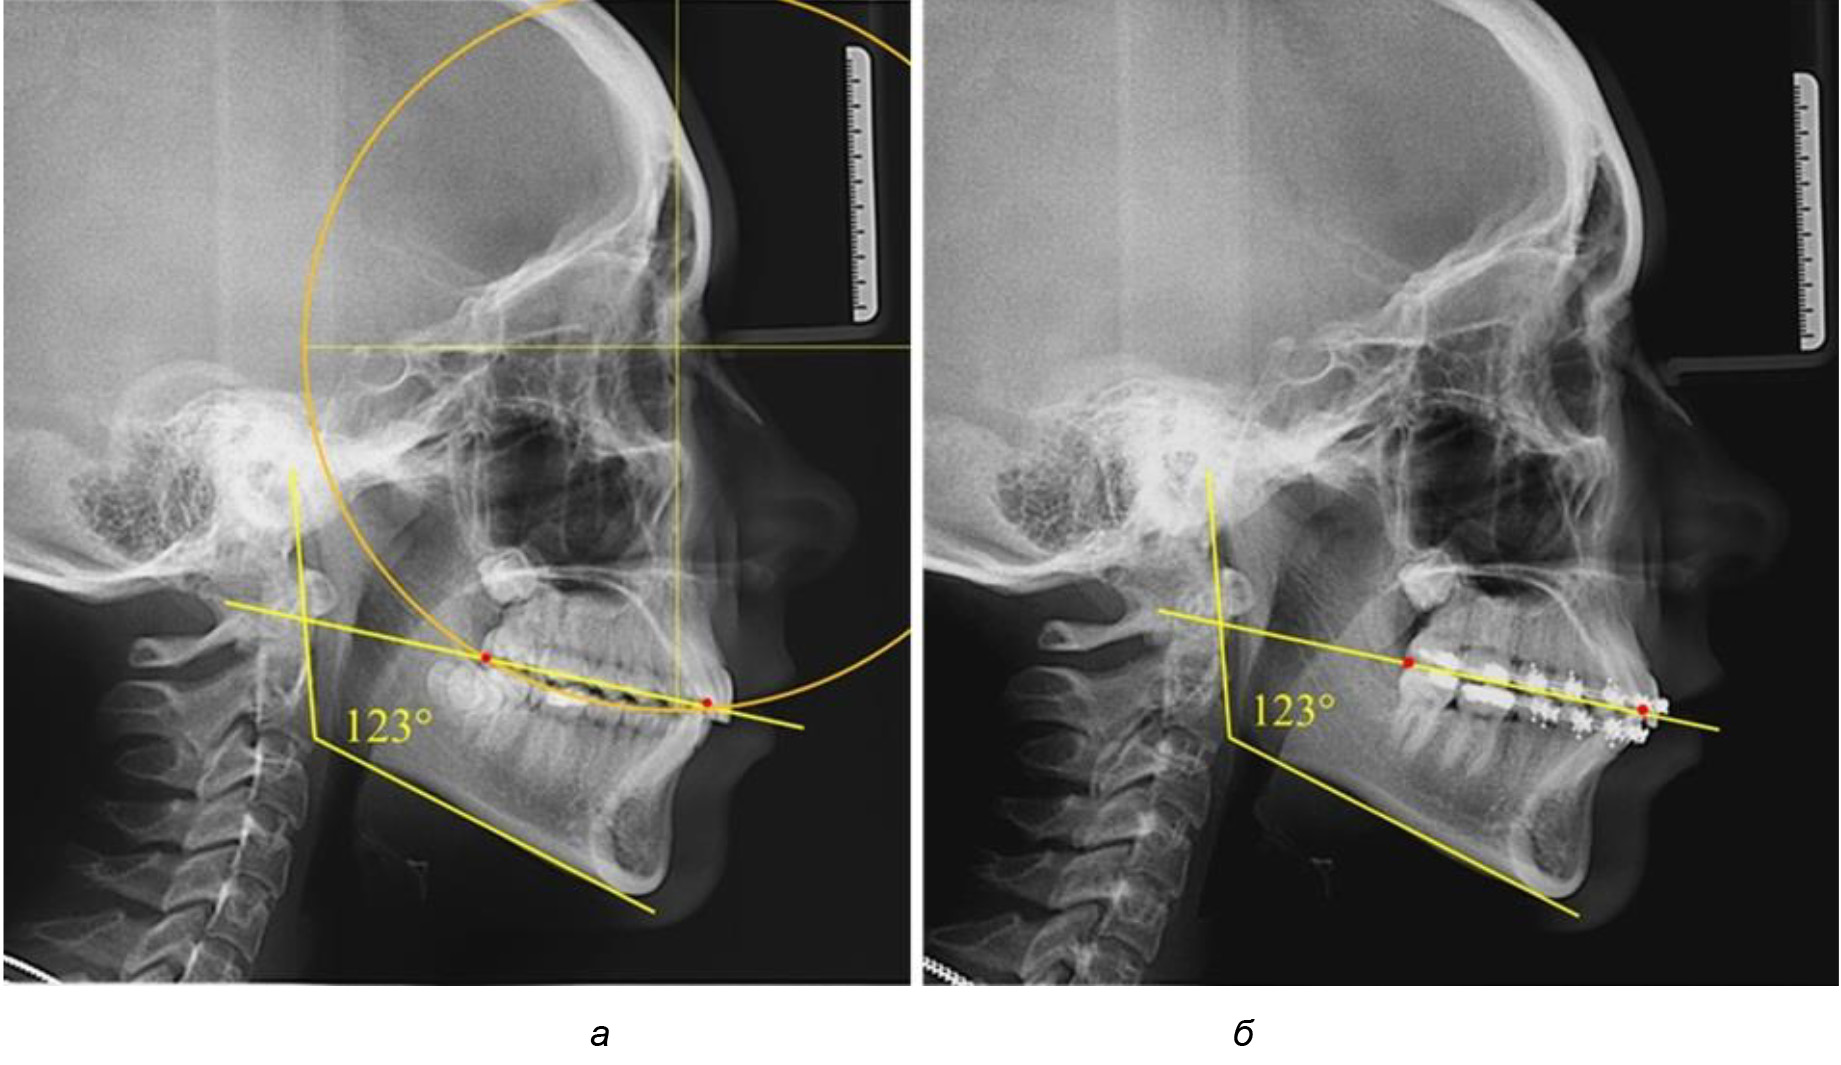

Рис. 2. Особенности кривой Spee на ТРГ (а) и ОПТГ (б) у людей с признаками вертикального роста

На рентгенограммах людей 2-й подгруппы (30 человек с нейтральным типом роста) величина угла нижней челюсти в среднем составила (120,34 ± 2,19) ° и характеризовала нейтральный тип нижней челюсти.

Глубина кривой Spee в среднем по 2-й подгруппе составил (3,54 ± 0,58) мм, что было незначительно меньше, чем при анализе аналогичного показателя 1-й подгруппы.

Достоверных различий с показателями, полученными при анализе ТРГ и ОПТГ, нами не отмечено (р ˃ 0,05). Деление величины радиуса круга к длине окклюзионной линии составило 1,612 ± 0,02, что, так же как и в 1-й подгруппе, было близким по значению к числу Фибоначчи (1, 618).

Рис. 3. Особенности кривой Spee на ТРГ (а) и ОПТГ (б) при нейтральном типе роста нижней челюсти